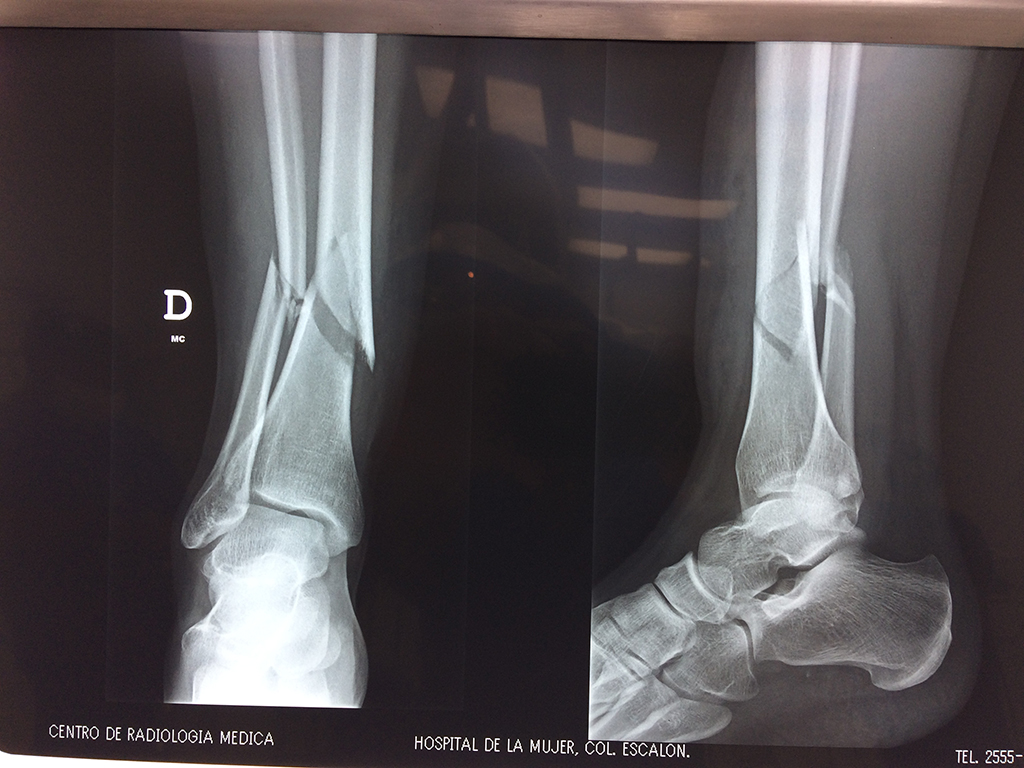

Cirugías de Peroné y Tibia

Aunque cada uno de estos huesos puede fracturarse por separado, normalmente la rotura es una lesión que se produce de forma conjunta

La mayor parte de las roturas implican a la parte proximal del hueso (parte del hueso próximo a la rodilla) o a la parte distal (parte del hueso cerca del tobillo).

Debido a la fina cobertura de piel que recubre la tibia y el peroné, las fracturas generalmente son abiertas, es decir, el hueso roto rasga la piel, atravesándola. Las fracturas de tibia y peroné generalmente se producen por un fuerte impacto o torsión.